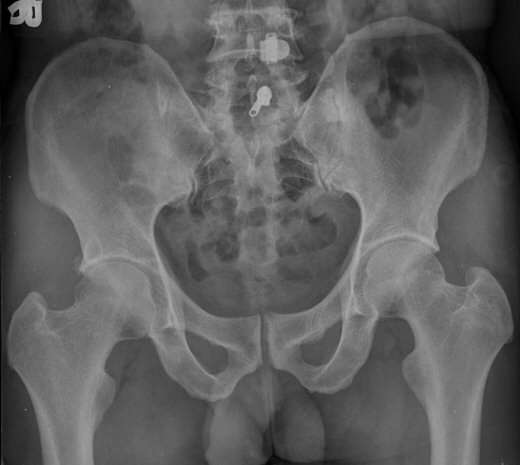

ŽÃËÀÚ¸¦ ¾ûµ¢ÀÌ °üÀý ¿ÜÃø Á¾´Ü¸é°Ë»ç ½Ã ÀüÇÏÀ屨(AIIS)¿¡¼­ ¼®È¸È­¼º À½¿µÀÌ °üÂûµÊ(»çÁø 2, 3).

ÃÊÁø ½Ã ½ÃÇàÇÑ ¹æ»ç¼± ÃÔ¿µ»ó ÀüÇÏÀ屨 ºÎÀ§¿¡¼­ ¼®È¸È­ À½¿µÀÌ °üÂûµÇ°í, 3ÁÖ ÈÄ ½ÃÇàÇÑ ÃÔ¿µ¿¡¼­

¼®È¸È­ À½¿µ ¼Ò½ÇÀÌ È®ÀεÊ.